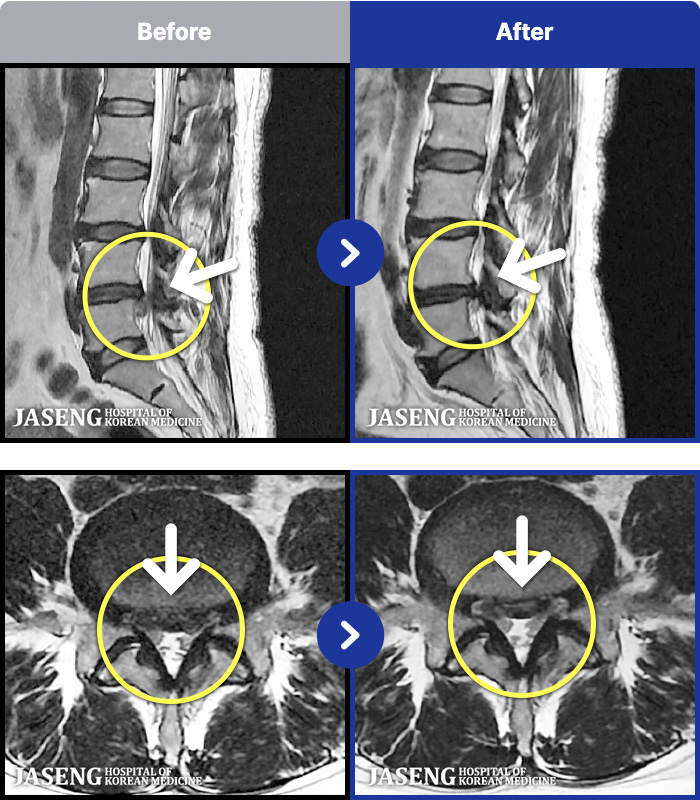

MRI ġ

86 MRI ũ ʸ Ȯϼ.